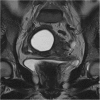

Endometrial cancer is the most common gynaecologic malignancy in developed countries and its incidence is increasing. First-level treatment, if no contraindicated, is based on surgery. Pre-operative imaging is needed for evaluation of local extent and detection of distant metastases in order to guide treatment planning. Radiological evaluation, based on transvaginal ultrasound, MR and CT, can make the difference in disease management, paying special attention to assessment of entity of myometrial invasion, cervical stromal extension, and assessment of lymph nodal involvement and distant metastases.